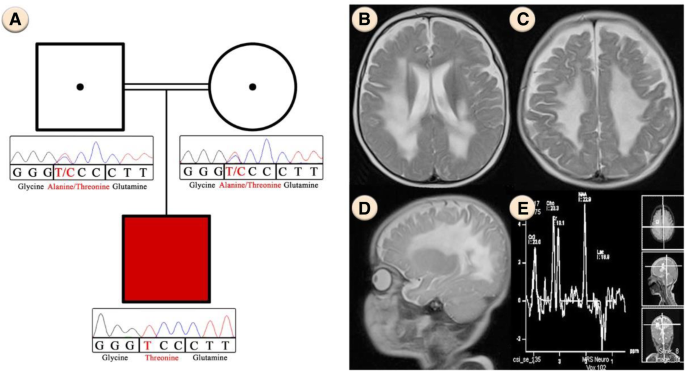

The proband (Fig. 1a), a boy who is the first child of an Iranian consanguineous family, was born after an uneventful pregnancy, but seven month after birth he developed some problems such as, malaise, insomnia, irritability, muscle stiffness and hypotonia. All general tests of the patient, including Complete Blood Count, Calcium, Phosphorous, Alkaline phosphatase, Total Vitamin D and Urine Analysis were normal. The patient’s abdomen sonography showed a normal size of kidney and spleen for his age. Brain magnetic resonance imaging showed nearly symmetrical abnormal changes in the areas of the periventricular white matter that was distributed in both centrum semiovale and has involvement of both middle cerebellar peduncles (Fig. 1b, c, d). Additionally, magnetic resonance spectroscopy which measures the amount of brain metabolites, indicated an increase in the lactate levels and a relative increase in the choline with respect to N-acetyl aspartate (NAA) in the periventricular regions of the patient’s brain, which is mostly reported in mitochondrial diseases (Fig. 1e).

a Pedigree of the family. Chromatograms represent homozygous and heterozygous state of c.355G > A variant in ISCA2 in the patient and his parents respectively. b, c Nearly symmetrical involvement of white matter in the axial view d Sagittal T2 view that shows extensive white matter signal change e Magnetic Resonance Spectroscopy that shows an increase in lactate levels and a relative increase in the choline with respect to N-acetyl aspartate (NAA)